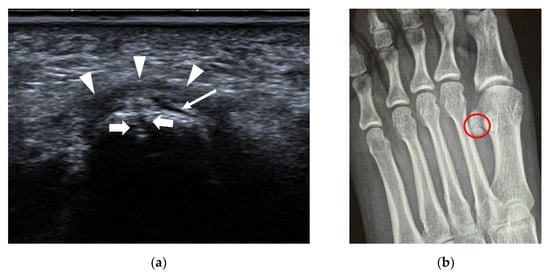

4.1.4. Foreign Bodies (FBs)

| Foreign bodies | / | strong reflector surrounded by hypoechoic tissue |